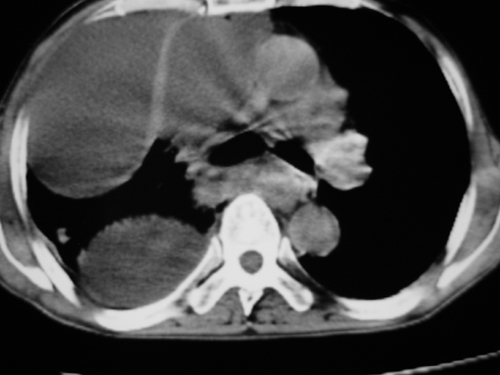

以下是引用yangyudong333在2008-4-29 5:46:00的发言:[br]1左上叶结节呈分叶状,边缘毛刺,考虑肺癌并纵隔淋巴结转移可能性大,结核待排,[br] [br]2右侧多发包裹性胸腔积液

以下是引用zsl6918在2008-4-29 9:15:00的发言:[br]右侧包裹性积液穿刺术后改变,肺内多发结节不除外转移可能。建议查胸水,问病史。